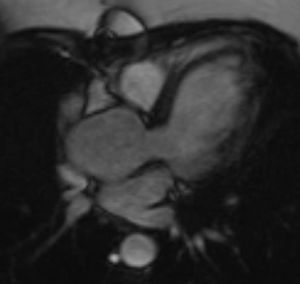

A. Valvular anomalyA.1. Bicuspid aortic valveA bicuspid aortic valve (BAV) is a congenital valvular anomaly found in approximately 30% of TS patients and it is not often clinically apparent.14

Identifying a BAV in asymptomatic individuals is important because they are at increased risk of infective endocarditis, hemodynamically significant stenosis (promoted by accelerated valve calcification), valve regurgitation (secondary to poor leaflet coaptation) and aortic aneurysm (due to the vicious cycle of increased stroke volume that promotes aortic root dilatation). For that reason, the anomaly requires regular medical evaluation and possibly surgery to prevent aortic dissection or rupture.14,16

Indeed, the aortic valve leaflet must be clearly visualized and echocardiography is the primary test for BAV that has been reported to be quite sensitive in diagnosing this anomaly in 89% of women with TS. However, echocardiography can be inadequate to view the aortic valve and, in these cases, CMR should be the next approach.4,14

In almost all the cases, BAV results from fusion of the right and left coronary leaflets, while the fused right coronary and non-coronary leaflets variant is much less common4,14 (Figure 2).